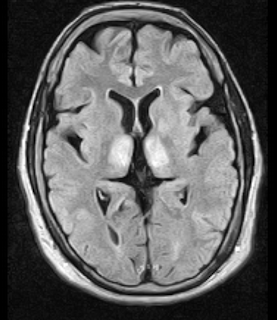

Fig.3: Axial MRI FLAIR image showing hyperintense signal in the mesial dorsal thalami, a common finding in Wernicke encephalopathy. This patient was nearly in coma when IV thiamine was started, he responded moderately well but was left with some Korsakoff type deficits.

Among paraclinical studies, magnetic resonance imaging (MRI) is currently considered the most valuable method to confirm a diagnosis of WE. MRI has a sensitivity of only 53%, but its high specificity of 93% means that it can be used to rule out the disorder. MRI studies typically show an increased T2 signal, bilaterally symmetrical, in the paraventricular regions of the thalamus, the hypothalamus, mammillary bodies, the periaqueductal region, the floor of the fourth ventricle, and midline cerebellum. Disruption of the BBB (blood brain barrier) has been seen in these regions in 6 of the 12 patients studied with contrastenhanced computed tomography (CT) or MRI scans. Importantly, the typical pattern of lesions on an MRI is observed in only 58 percent of patients.